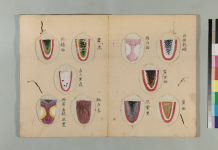

胸脇苦満ノ毒、浅薄ナル者ノ圖也。

按之而知ノ傳、圖ノ如ク、

脇下肋骨ノ端ヲ指ニテカヽゲミルニ、コタユルモノアリ。

是薄キ苦満ノ毒ナリ。

又、心下ヲ按テ少シクコタユルモノナリ。

是即痞鞕ナリ。世二積聚ト号スルモノ、此ノ證多シ。

又圖ノ如ク、苦満アリテ、心下痞硬甚シキモノアリ。

此時ハマヅ苦満ヲサシ置テ、痞鞕ヨリ攻ベシ。

原文の緑の下線部①〜③について

腹部の邪の現れ方についてです。

①厚深ナルモノハ見易ク

(邪が深くにあるものは見やすい)

②浅薄ナルモノハ見難シ。

(邪が浅くにあるものは見難い)

③毒浅薄ナルカ、如クニシテ、大二深キモノアリ。

(邪が浅くにあるようにみえても実は深くにある場合がある)

③は邪が腹底にあり、

表には現れないものである。

と記載されています。